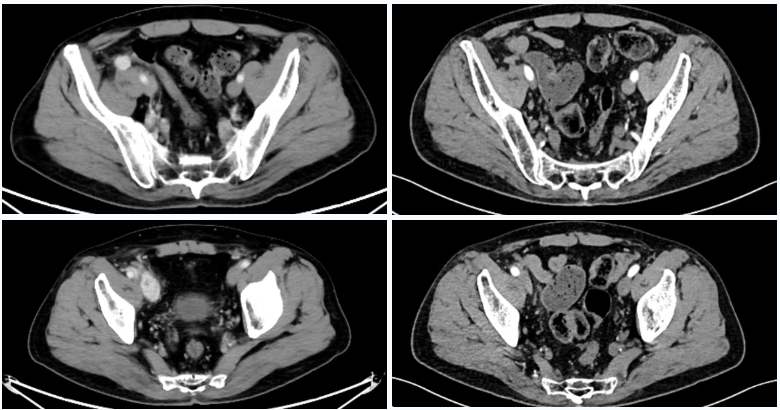

△2023年2月患者基线时CT(左)与2024年4月时CT(右)检查所见对比

△2025年8月疗效评估时患者CT检查(右)较基线(左)对比